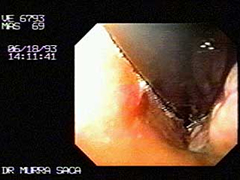

Carcinoma del cardias gástrico:

Hacía un mes a este diagnostico presento un sangramiento del tubo digestivo superior por lo que fue ingresado a un instituto de seguro social el diagnostico de alta fue de gastritis erosiva, el paciente siguió mal de salud por lo que pidió una segunda opinión.

Nota: Después de una endoscopia de emergencias por un sangramiento activo es necesario practicar este estudio por segunda vez ya que la sangre impide visualizar algunas patologías.